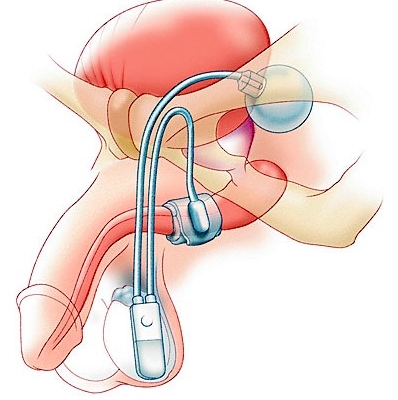

Urinary Incontinence

Loss of bladder control can significantly affect daily living. Dr. Jo  specializes in identifying the underlying cause and offering personalized medical or surgical solutions to restore confidence and comfort.